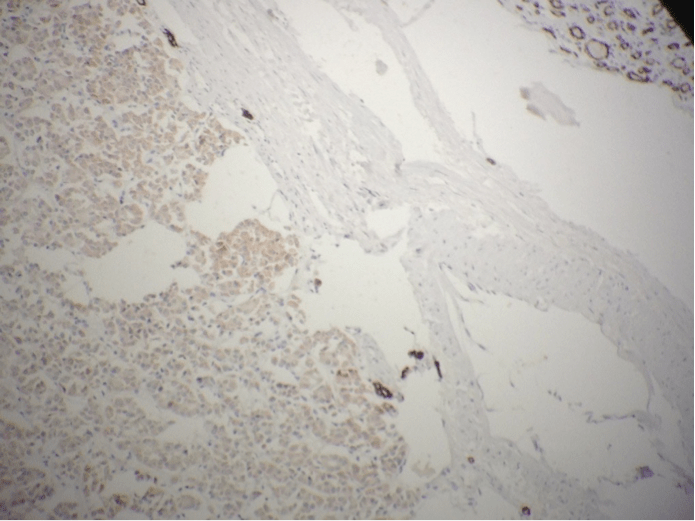

Absence De Positivite Au Niveau De La Proliferation Femorale

Absence De Positivite Au Niveau De La Proliferation Femorale. Recherche d'une hyperfixation au niveau du genou gauche avant chirurgie de la hanche. Le fémur est l’os longiligne qui forme le squelette de la cuisse.

Les raisons de l’amputation fémorale varient. Recherche d'une hyperfixation au niveau du genou gauche avant chirurgie de la hanche. Les bonnes pratiques d'hygiène, notamment le lavage des mains, restent un grand défi au burundi, puisque seulement 6 pour cent de la population a accès aux services d'hygiène de base en raison.